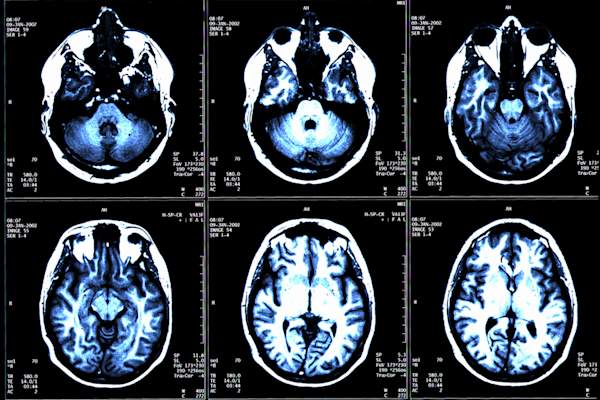

DMTS并非旨在帮助日常症状,因此您不一定会告诉他们是否正在工作,但是,目标是保持MS在控制下。奥纳丹博士说:“我们所寻求的临床术语是一个禁智的东西:”没有疾病活动的证据,“”简而言之,这意味着您停止有MS复发或攻击,并且没有任何新的大脑病变对MRI的证据。“这是一个可实现的目标,这是我们在所有患者中努力的目标,”他说。